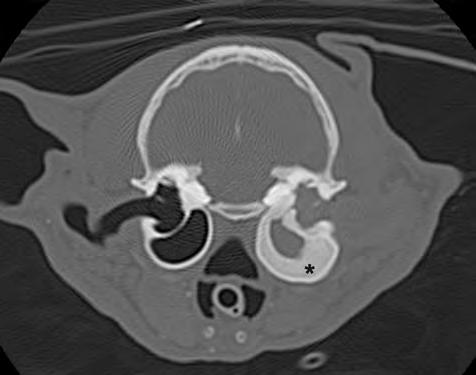

1. Radiografías de la cabeza de un gato maine coon de un año de edad. (A) Proyección lateral. (B) Proyección dorsoventral. (C) Rostro 10º ventrodorsocaudal oblicua.

Se presentó en consulta un gato macho castrado de raza maine coon, de un año de edad y 5,8 kg de peso, remitido con historia de otitis externa desde hacía un mes.

En la exploración otológica se visualizó una masa en el conducto auditivo externo izquierdo, apreciable desde la abertura del pabellón auricular. La masa era sólida, poco móvil y obstruía totalmente el canal auditivo. El resto del examen físico y pruebas de enfermedades víricas fueron normales. En el análisis sanguíneo se evidenció neutrofilia con desviación a la izquierda y trombocitosis.